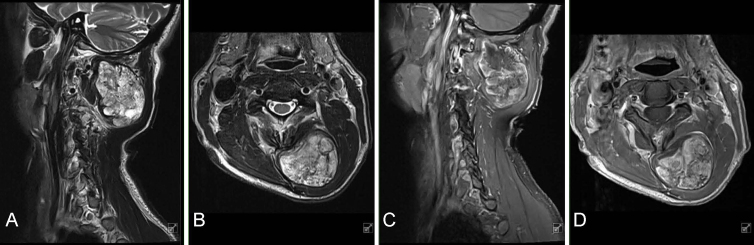

背景:骨外骨软骨瘤是一种界限明确的骨软骨性病变,起源于没有骨连续性的软组织。骨外骨软骨瘤可能出现在关节旁位置,尽管很少有报道的病例发生在脊柱附近。临床诊断仍然具有挑战性,因为这些肿瘤很难与其他骨化软组织病变区分开来。治疗包括观察或切除。在这里,作者提出一个罕见的病例骨外骨软骨瘤附近的颈椎。观察:56岁男性,表现为可触及的左侧椎骨旁枕骨下肿块,缓慢进展超过5年。患者无症状,神经学检查无局灶性。MRI显示左侧枕下区约6厘米边界清晰的非均匀肿块,与脊柱或颅骨没有直接接触。在t2加权MRI上发现一个低信号囊,在T1和t2加权MRI上发现多个低信号分隔。肿瘤生长缓慢提示为良性肿瘤。胸部、腹部和骨盆的CT检查排除了恶性肿瘤。手术干预被提出并被患者接受。术后2个月,影像学显示无复发,患者无症状,活动范围改善。结论:在诊断骨软骨旁肿块时应考虑骨骼外骨软骨瘤。https://thejns.org/doi/10.3171/CASE25468。

Observations: A 56-year-old male presented with a palpable left paraspinal suboccipital mass that had slowly progressed over 5 years. The patient was asymptomatic and the neurological examination was nonfocal. MRI revealed an approximately 6-cm well-circumscribed heterogeneous mass in the left suboccipital area that lacked direct contact with the spine or calvarium. A hypointense capsule on T2-weighted MRI and multiple hypointense septations on T1- and T2-weighted MRI were identified. The slow rate of tumor growth suggested a benign tumor. CT imaging of the chest, abdomen, and pelvis was obtained to rule out malignancy. Surgical intervention was offered and accepted by the patient. At 2 months postoperatively, imaging demonstrated no recurrence, and the patient was asymptomatic and had improved range of motion.